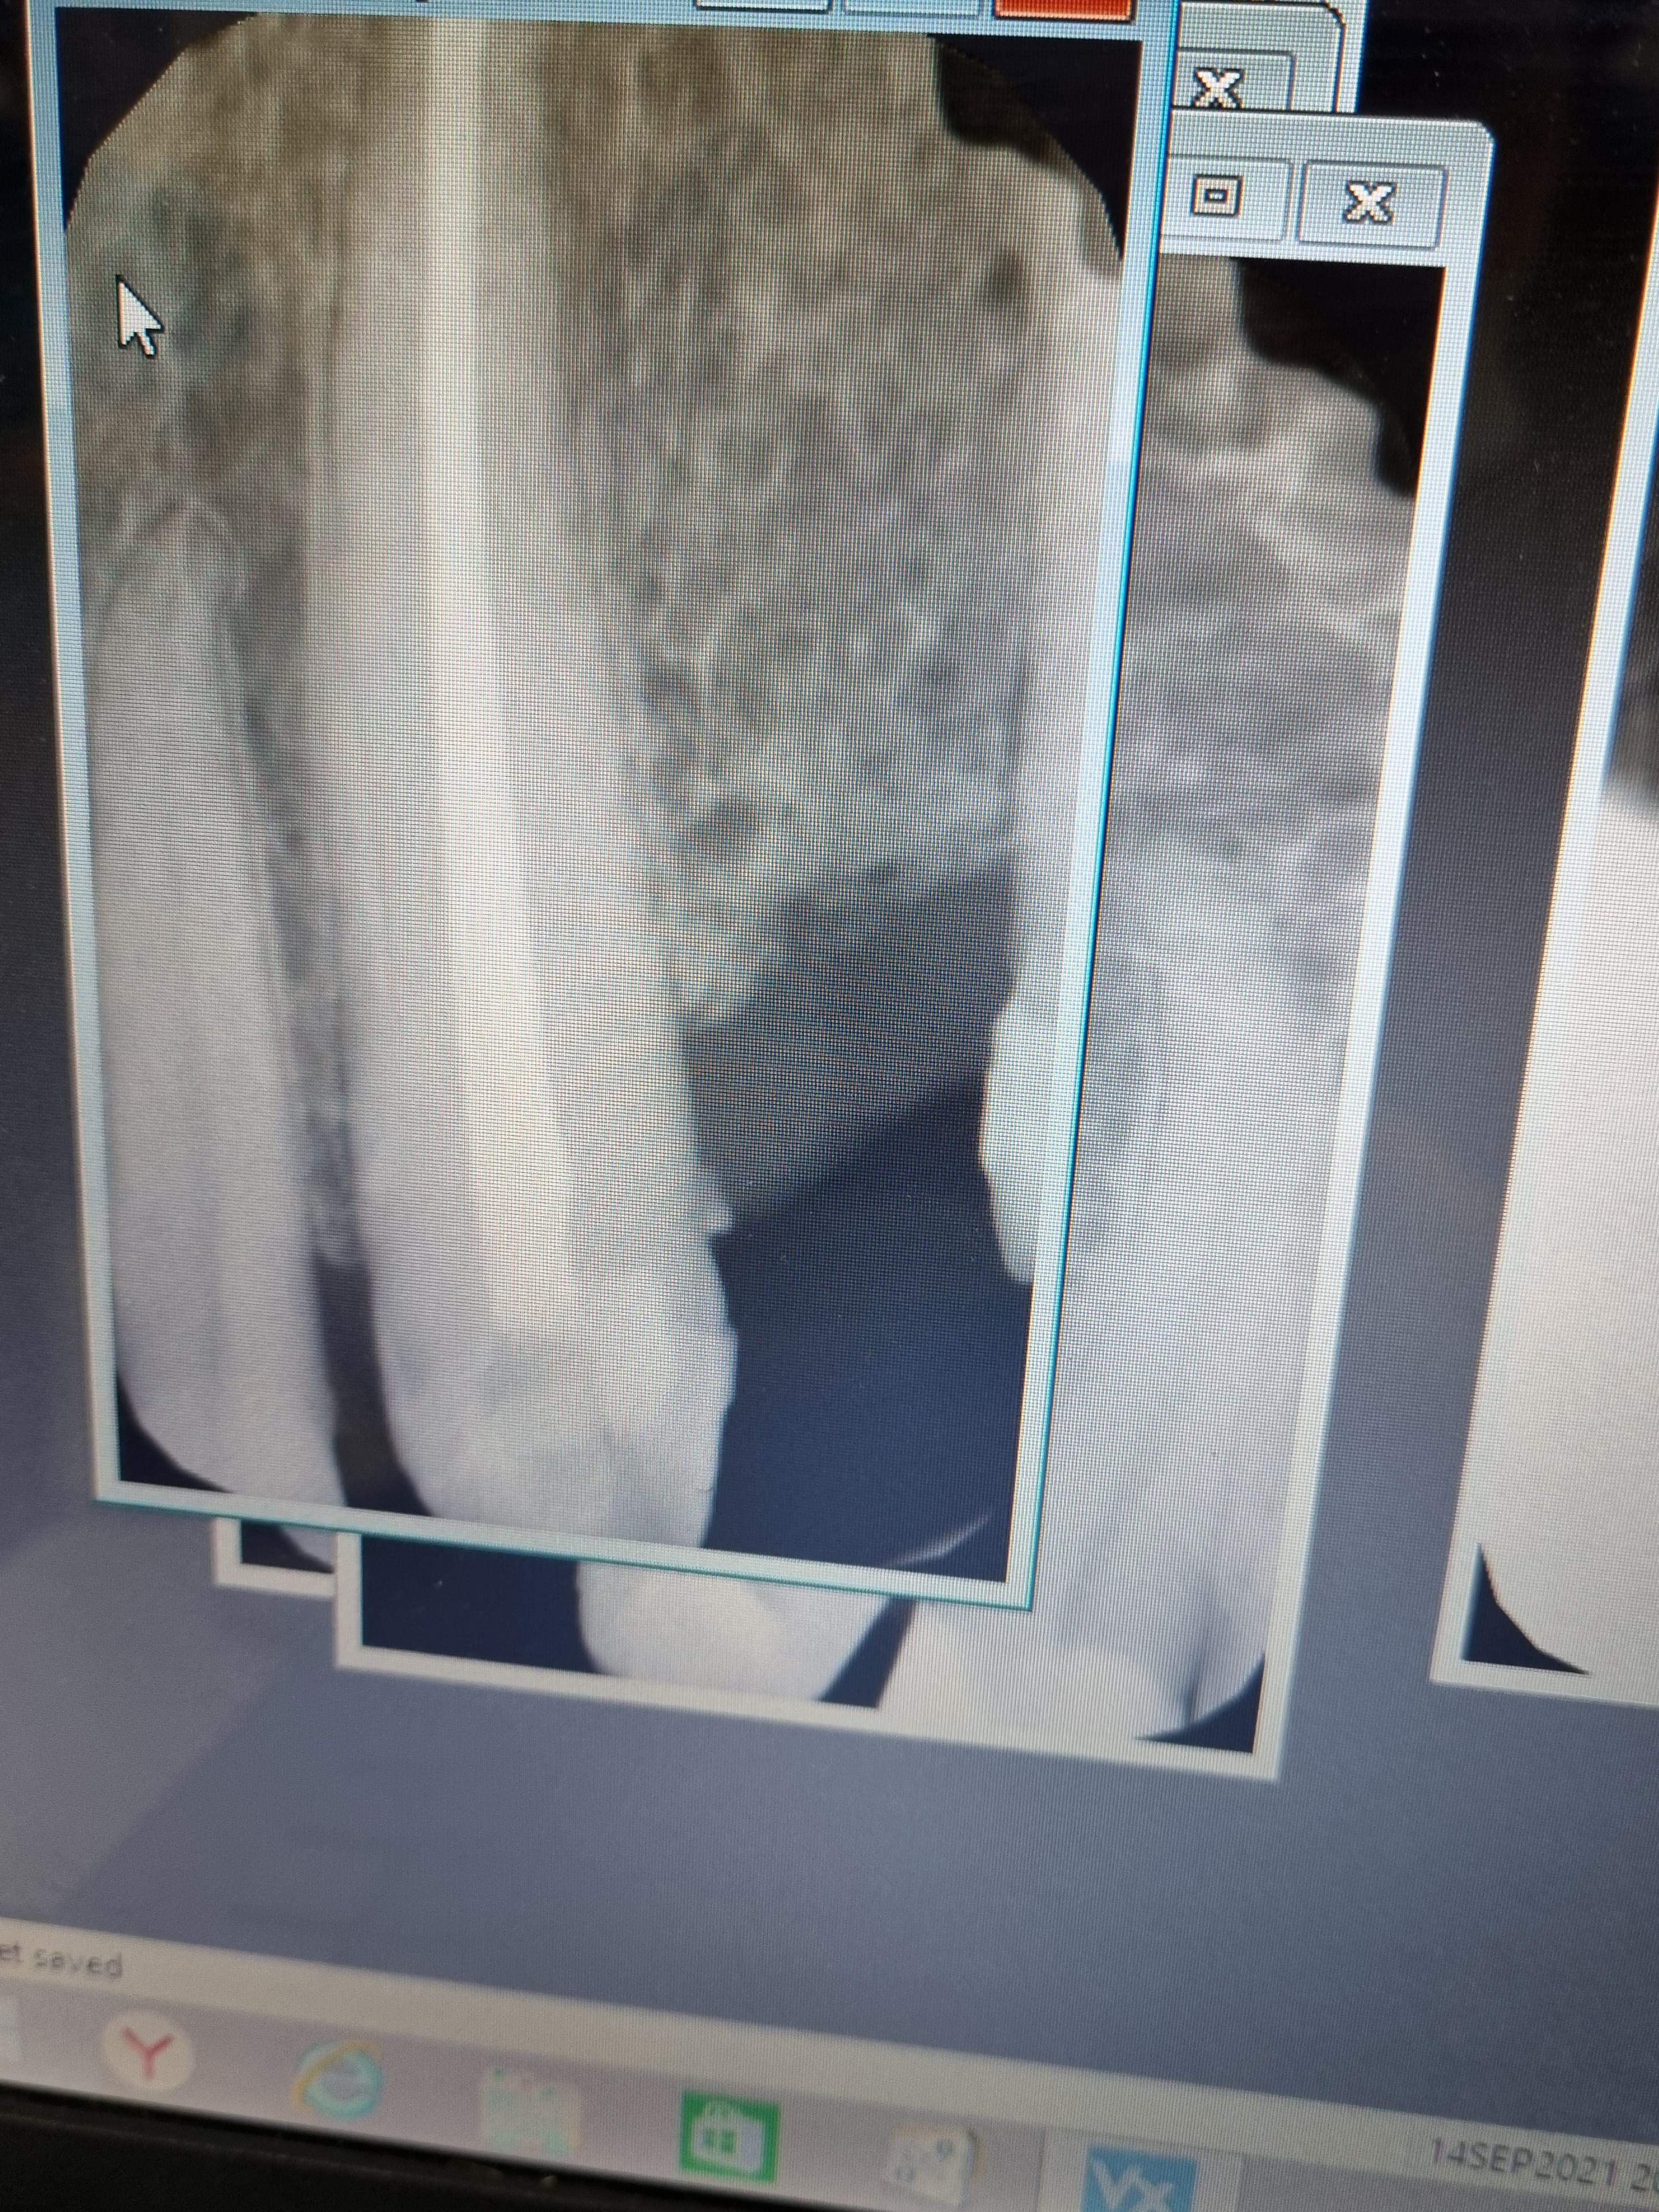

Устранение хронического апикального периодонтита зуба 1.7 с временным восстановлением коронкиСмотреть работуСрок лечения:2 визитаСумма лечения:14 337 руб.